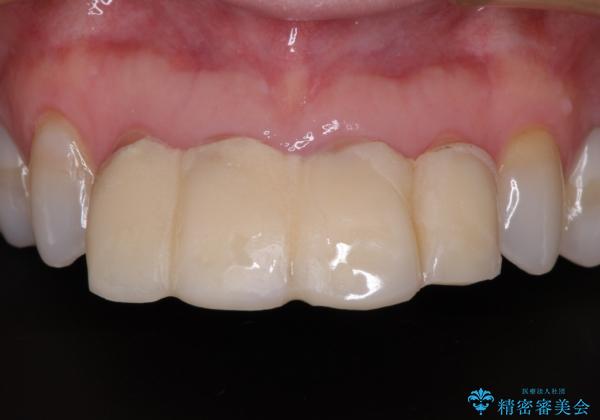

前医で仮歯を装着する前の口元の写真をいただき、咬み合わせや形態を参考にしながら仮歯で仕上がりをイメージし、最終的に満足のいくオールセラミッククラウンを装着することができました。